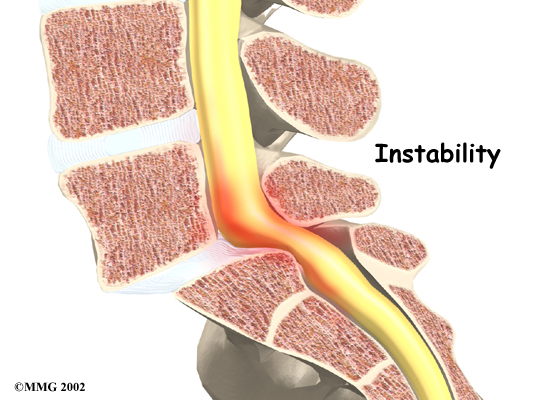

Spinal instability: can cause spinal stenosis. Spinal instability means that the bones of the spine move more than they should. Instability in the lumbar spine can develop if the supporting ligaments have been stretched or torn from a severe back injury. People with diseases that loosen their connective tissues may also have spinal instability. Whatever the cause, extra movement in the bones of the spine can lead to spinal stenosis.